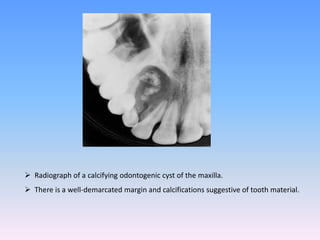

 Radiograph of a calcifying odontogenic cyst of the maxilla.

 There is a well-demarcated margin and calcifications suggestive of tooth material.

Axial CT image shows unilocular radiolucencies with a well-defined border in the

right mandible canine to molar area and buccolingual bony expansion.

Radio-opaque materials are located at the periphery.

Coronal CT image shows unilocular radiolucencies with a well-defined border in

the right mandible canine to molar area and buccolingual bony expansion.

CT FINDINGS